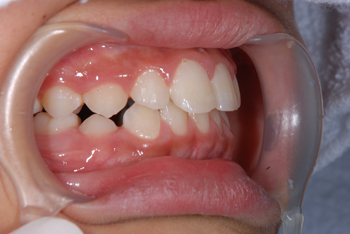

Ⅰ期治療(拡大床による骨格治療)で、少しワイヤーを使うだけでここまでキレイに並びました。

After

小学校3年生から始めて中学1に上がるまで期間はかかりましたが、キレイに並んで本人もご家族もご満足いただけました。お子様の歯並びは、将来のお子様の歯の健康や心身の健康に大きく関わってきます。また、歯並びが悪いとどうしても磨き残しや食べかすが詰まりやすくなり、若いうちからむし歯によって歯が悪くなることが多々有る上、判断が遅れⅡ期治療からになると、抜歯を余儀なくすることもあり得ます。